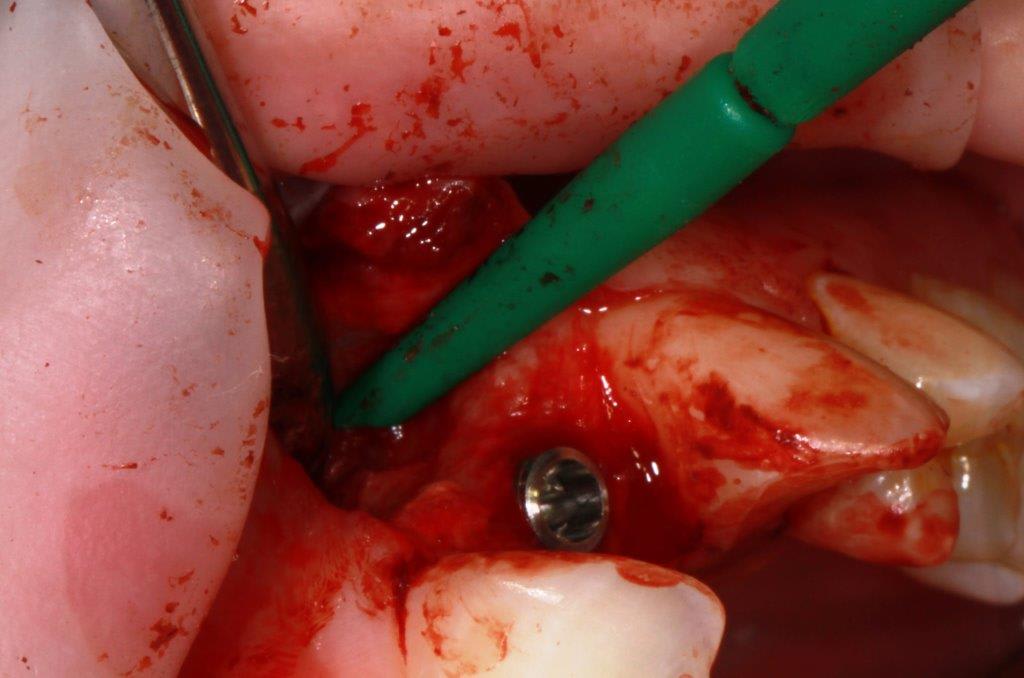

pour ceux que ça intéressent, une petite utilisation d'expansion de la paroi palatine, sur une avulsion d’incisive(racine fendue). toutes mes excuses pour la mauvaise qualité des photos.